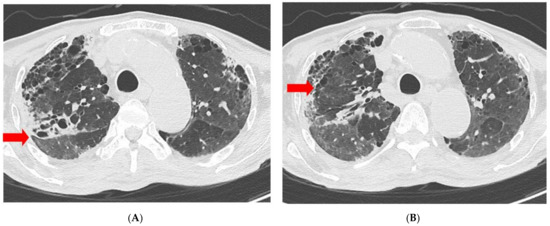

| Chest radiography | GGO in BLLF | Increased GGO | Increased GGO | Decreased GGO | Decreased GGO | Decreased GGO | No interval change | No interval change |